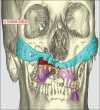

Rationale: The successful utilisation of three dimensional (3D) techniques in engineering a titanium patient specific implant (PSI) for a patient who underwent hemimaxillectomy following post COVID mucormycosis infection.

Treatment: The patient was operated for mucormycosis followed by reconstruction with patient specific implant.

Take away lessons: The advances in the use of PSI by integration of 3D printing and computer aided design computer aided manufacturing (CAD-CAM) technology for extensive and challenging defects in the maxillofacial region have been highlighted in this case report.